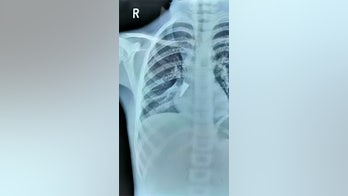

January 6, 2020 Doctor pulls pen cap from girl's lung after she accidentally inhaled it weeks ago Neither the girl nor her grandfather thought much of the incident when it occurred.